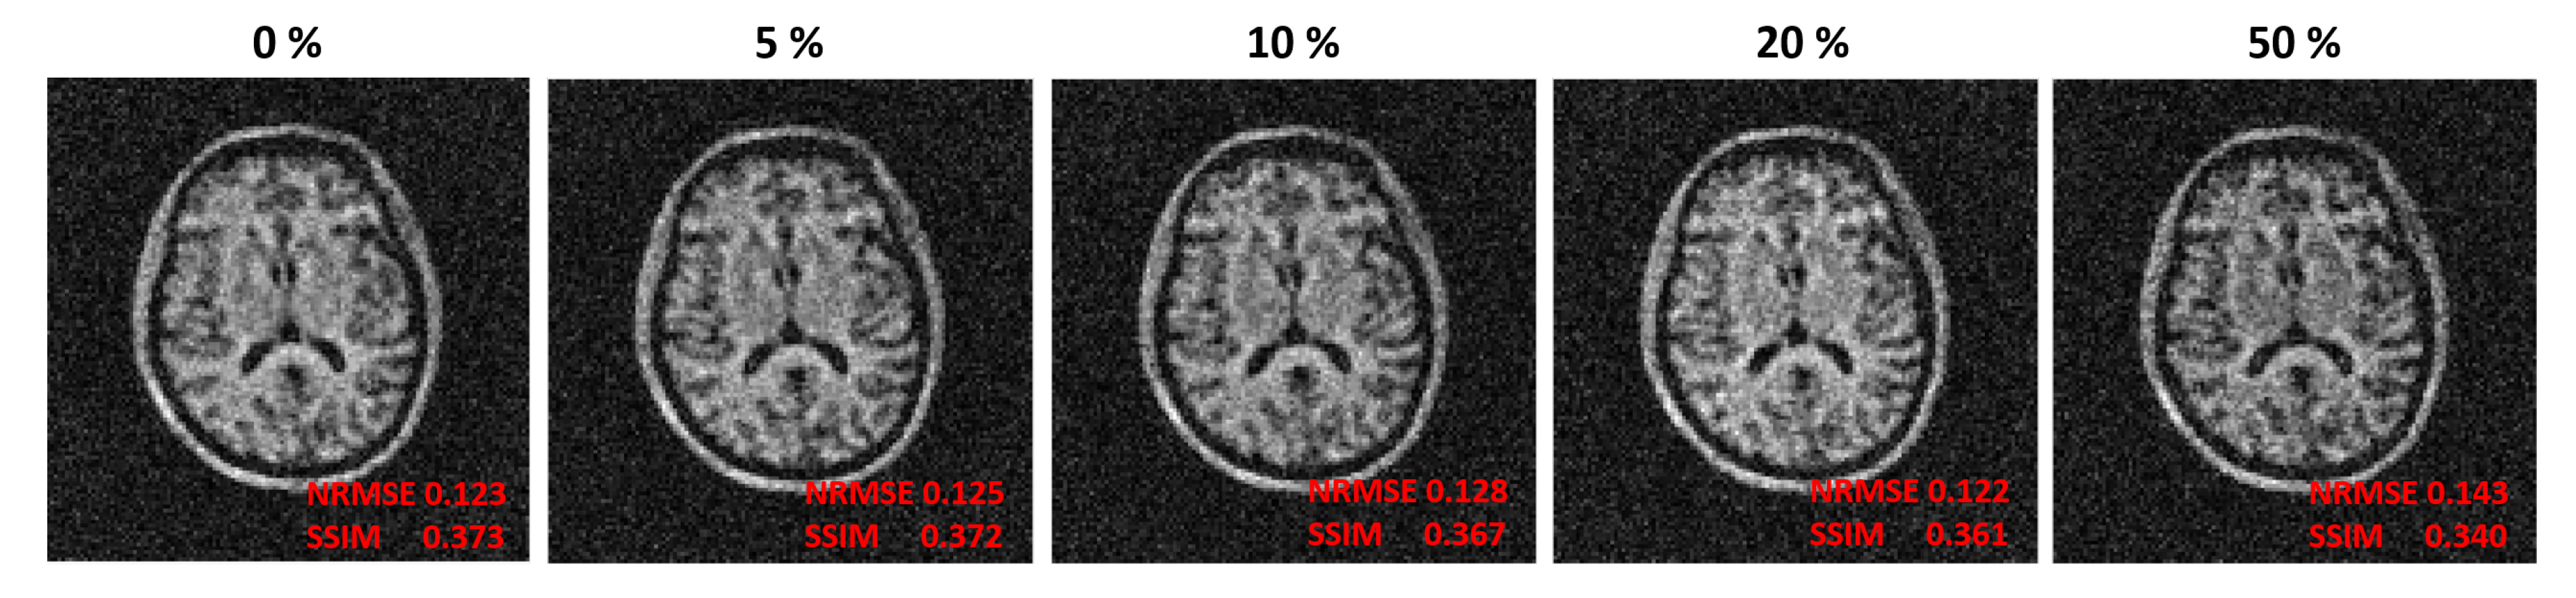

| Threshold | = | Total | ||

|---|---|---|---|---|

| 0 | 4096 MB | 11,520 MB | 0.7 MB | 15,617 MB |

| 5% | 4096 MB | 338.8 MB | 0.7 MB | 4436 MB |

| 10% | 4096 MB | 170.7 MB | 0.7 MB | 4267 MB |

| 20% | 4096 MB | 84.5 MB | 0.7 MB | 4181 MB |

| 50% | 4096 MB | 45.1 MB | 0.7 MB | 4142 MB |